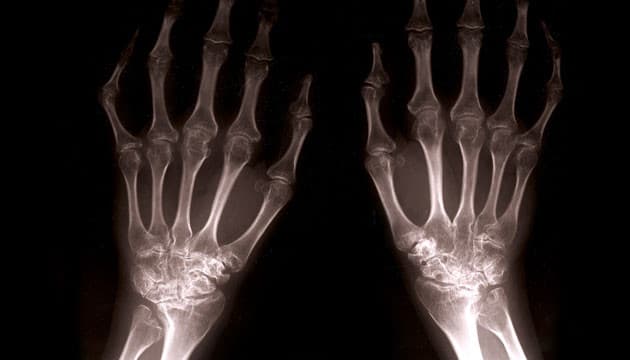

Patienter med reumatoid artritis (RA) har en større risiko for at udvikle kardiovaskulær sygdom og kræft end baggrundsbefolkningen. Studier af effekten af tumornekrosefaktor (TNF)-inhibitorer har antydet, at disse biologiske lægemidler, ud over at gave en gavnlig effekt på gigtsygdommen, kan nedsætte den kardiovaskulære risiko, mens januskinase (JAK)-inhibitorer muligvis kan forhøje denne risiko. Oral Surveillance-studiet fokuserer på langtidsbivirkninger ved at sammenligne JAK-inhibitoren tofacitinib med en TNF-inhibitor hos 1.455 patienter med RA, som følges i fire år. Forfatterne konkluderer, at behandling med tofacitib er associeret til ca. 30% højere risiko for kardiovaskulær sygdom og 50% højere risiko for kræft.